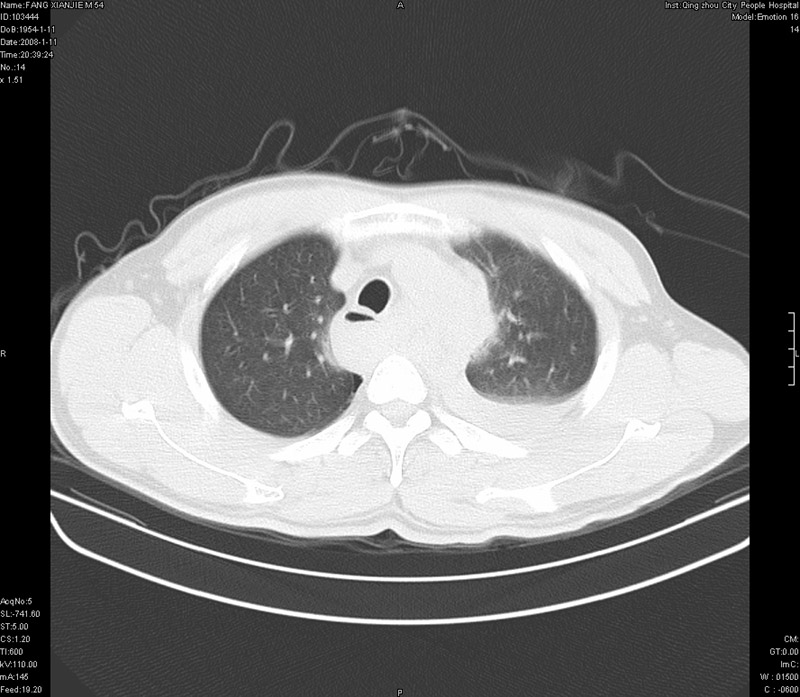

男性,40岁。胸部被车压伤伴胸痛1小时来院就诊。检查:一般情况尚可,血压110/80,胸部及上腹部压痛。结果在三天后公布。骨窗在横断位、冠矢状显示肋骨、胸椎、和胸骨未见骨折征象。

ct11308:胸部外伤1小时(证实病例) (2008-1-13 16:2)结果如下:病人入院后两小时后症状加重,8小时后在征得病人家属同意做了ct增强扫描。如下图。最终临床诊断:外伤性胸主动脉破裂并纵隔内血肿。由于有运动性伪影,胸骨在矢状面重建的图像似有骨折征,这是一种假象,我们称之为“假骨折”,这在多层ct重建中经常性遇到,必要时要结合横断图像鉴别之。现在,病人的一般情况较差,是否要手术家属尚有争议,如果手术修补,难度较大,需要专门预定制作固定支架。

当然,对于该病例,其它非重要的诊断还有:右侧少量气胸;左侧胸腔积液;左侧轻度肺挫裂伤。对于纵隔内血肿,我们曾经遇到过多例,也有怀疑主动脉的破裂,但是,均未得到具体出血部位的明确诊断。